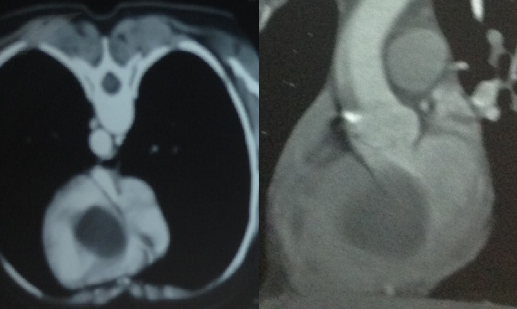

A 35-year-old female presented with a history of fatigue, palpitations, syncopy, and heaviness of chest for the past year. Her symptoms were more pronounced on exertion and relieved on rest. She did not have any other associated problems. She did not have a significant past medical or surgical history. She was afebrile with Hb. of 13.1 g/dl, WBC 10*10^9/L on admission. Her blood type was A+, and HCV and HIV blood tests were negative. Echinococcus granulosus IHA titer was less than 1:16 (negative). On two-dimensional transthoracic echocardiography EF was 65% and there was evidence of LVOT obstruction. A cystic mass measuring 40 × 35 mm within the basal interventricular septum was discovered (Figure 1). Computed tomography of the chest showed a cyst in the interventricular septum and no other cysts were found (Figure 2). MRI showed the brain to be normal.